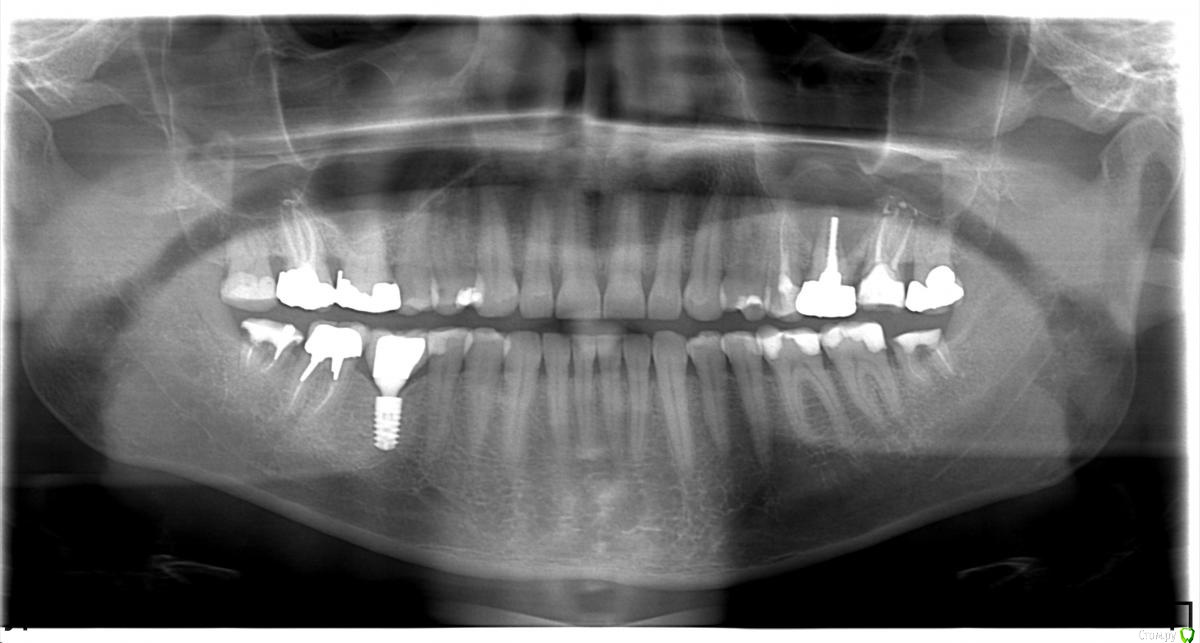

LeoRuss Опубликовано 31 января, 2017 Поделиться Опубликовано 31 января, 2017 (изменено) Вот, неожиданно тема месячной давности http://forum.stom.ru/topic/34389-analiz-kt-i-panoram-nuzhno-mnenie-profi/ получила продолжение:По данным свежей томографии предлагается выскрёбывание полости кисты и подсадка кости, тк естественным путем, по словам хирурга, она сама не зарастет в связи со значительным размером. Т.е. останется открытый типа свищ (соустье?) между гайморовой и ротовой, плюс о последующей установке импланта в такой ситуации не может быть и речи. Поскольку это противоречит мнению уважаемого Bier : http://forum.stom.ru/topic/34389-analiz-kt-i-panoram-nuzhno-mnenie-profi/?p=573225, прошу вас, мэтры, высказать свои мнения и рекомендации по этой малоприятной ситуёвине. Вот новое КТ в Galileos: https://yadi.sk/d/eeX5n1Jd3C2Lxm(140Мб)старое КТ от Vatech и панорамы есть в вышеназванной теме, но в конце 2015 никаких отклоненийна снимках по 26ке заметно не было, хотя нет, на КТ было: перфорация титановым штифтом в небном корне. новую панораму для вашего удобства дублирую здесь Спасибо! Изменено 31 января, 2017 пользователем LeoRuss Ссылка на комментарий